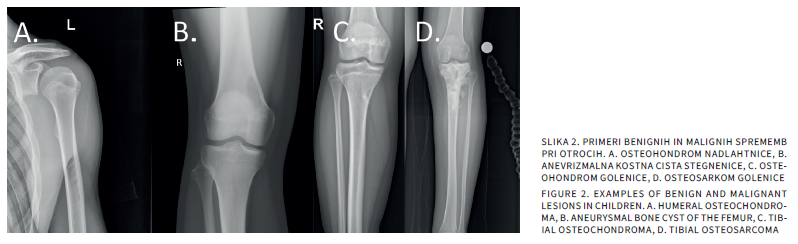

Musculoskeletal pain is one of the most common reasons for pediatric visits. Although the causes are often benign, such as growing pains or overuse syndromes, similar symptoms may also conceal serious orthopedic conditions, including Perthes disease, slipped capital femoral epiphysis, or neoplasms. This article presents the diagnostic approach to children with joint pain and provides a detailed overview of the most frequent orthopedic entities, emphasizing the importance of recognizing red flags and timely collaboration between the pediatrician and the orthopedic surgeon.